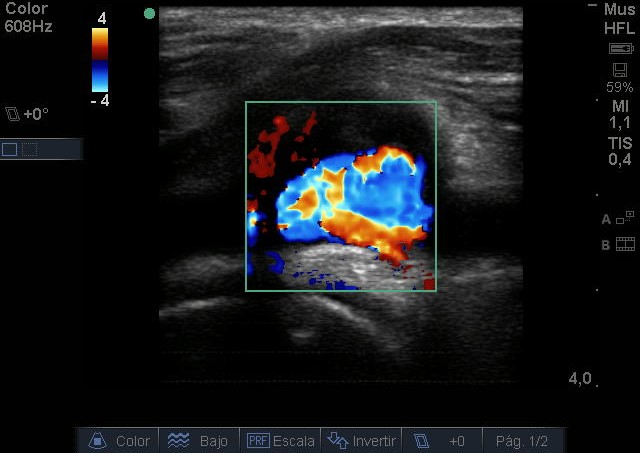

Se visualiza aneurisma de 2 centímetros con imagen compatible con trombo intramural. En modo Doppler flujo turbulento. Realizamos ecografía de rodilla contralateral y aórtica sin hallazgos reseñables.

Juicio Clínico: Aneurisma poplíteo con trombo intramural.